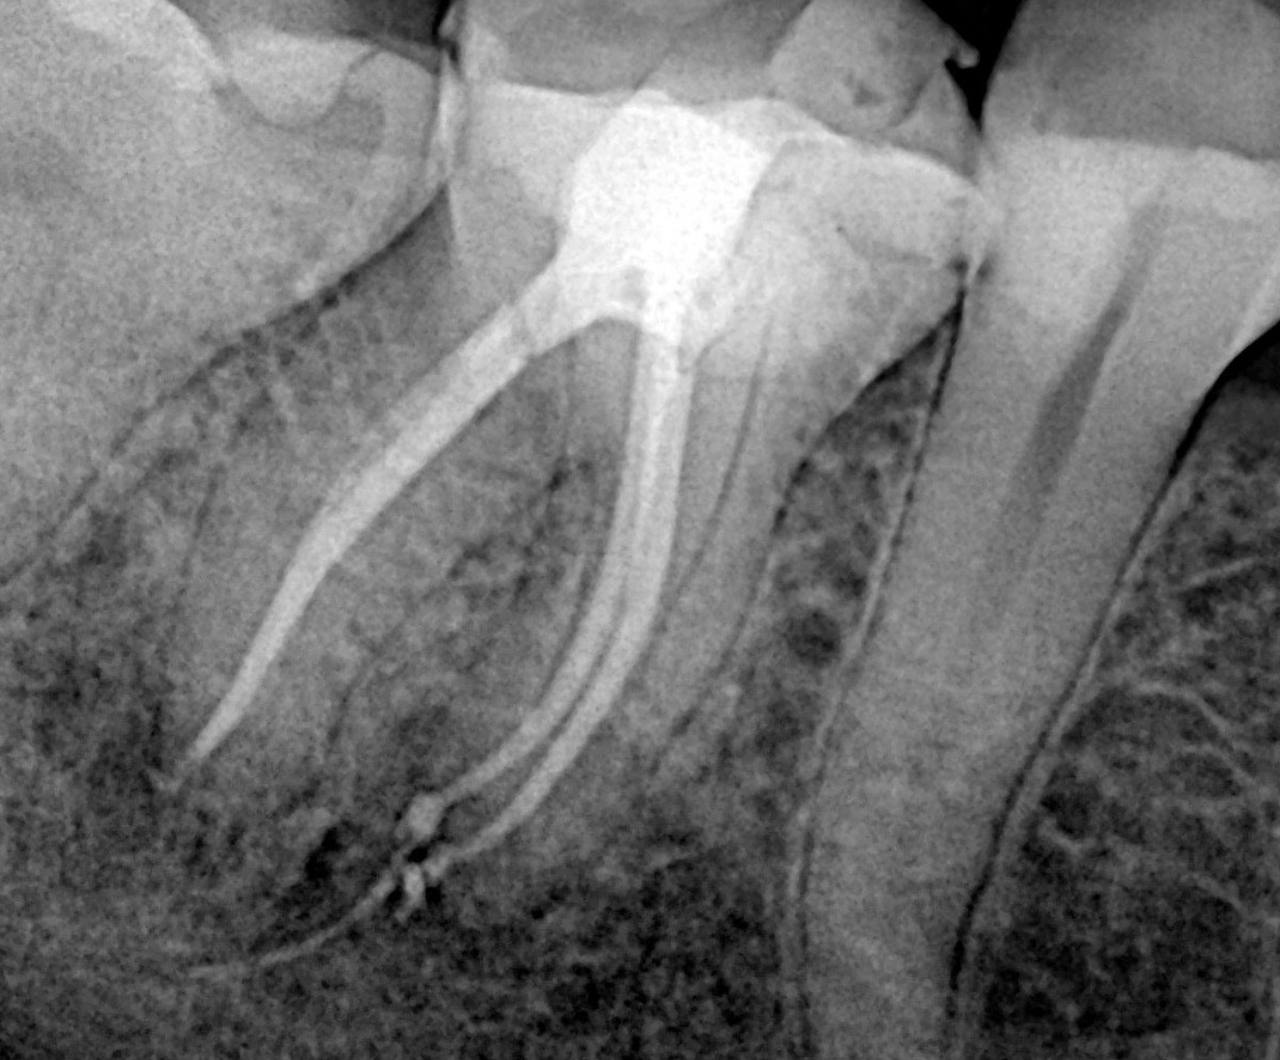

4. What type of perforation is being treated by an endodontist in this X ray?